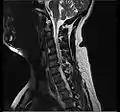

- Magnetic resonance imaging (MRI) without contrast is a diagnostic test that produces three-dimensional images of body structures using powerful magnets and computer technology. It can show the spinal cord, nerve roots, and surrounding areas, as well as enlargement, degeneration, and tumors. It shows soft tissues better than CAT scans. An MRI performed with a high magnetic field strength usually provides the most conclusive evidence for diagnosis of a disc herniation. T2-weighted images allow for clear visualization of protruded disc material in the spinal canal.

MRI scan of cervical disc herniation between C5 and C6 vertebrae.

MRI scan of cervical disc herniation between C6 and C7 vertebrae